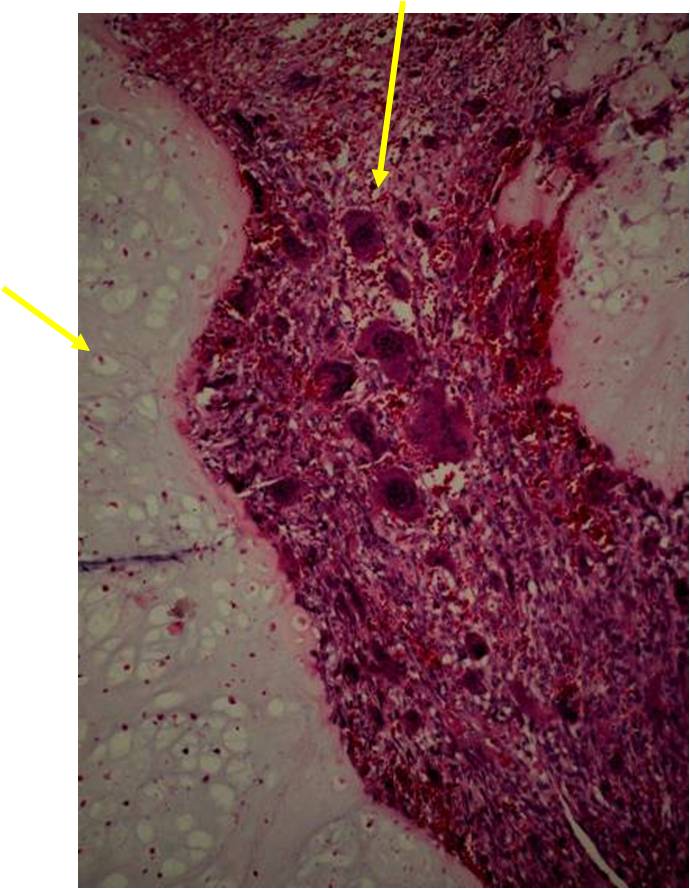

Junction of cartilaginous and noncartilaginous components is sharp and distinct. There are no dedifferentiated areas admixed in the middle of the cartilaginous areas

(Right Arrow) Dedifferentiated Component

- Chondrosarcoma component is often grade I (Low Grade Hyaline Type Cartilage)

- Dedifferentiated component

- Osteosarcoma is third most common dedifferentiated component